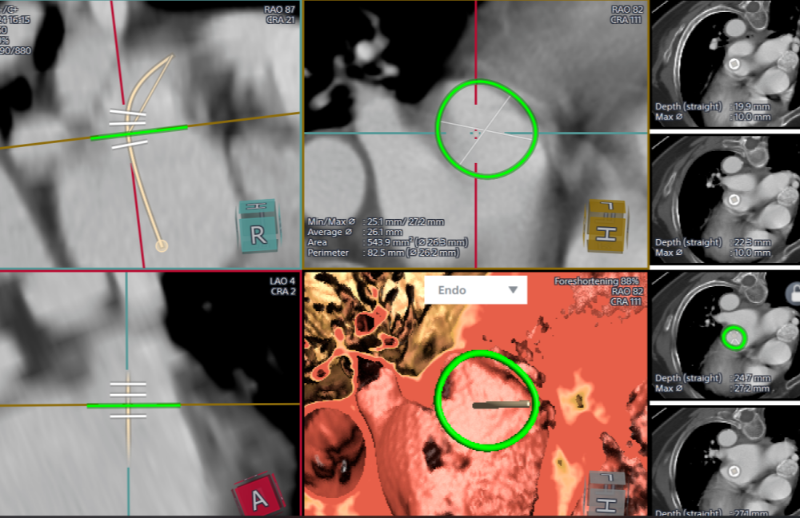

经过完善的术前CT和全面的Truplan软件术前分析准备。在介入室的全面配合下完成该患者的术前准备工作,谢桂庭进行房间隔穿刺,精准定位穿刺位点。行左心耳造影,造影结果显示开口28mm左右,深度32mm左右。结合术前Truplan结果以及术中DSA测量结果,选用WATCHMAN 33mm封堵器进行封堵。

在团队紧密配合下,谢桂庭巧妙地将封堵器坐落到心耳上缘囊袋,同时施加逆时针的力减少下缘露肩。缓慢平稳展开,一次到位,实现平口封堵。在DSA下进行牵拉实验,封堵器回弹明显无位移,提示稳定性良好。左心耳封堵器无露肩,无残余分流,压缩比13%-25%,满足PASS原则评估,释放封堵器。